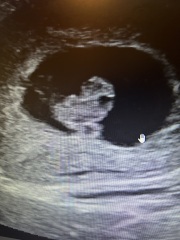

So I had a scan today and I am delighted to learn my little munchkin is ahead. Measuring one day ahead of schedule. (The previous scan measured one day behind, so munchkin has been actively growing these past few days) Pictures attached show in one picture the little one is showcasing the limbs. In the other picture we are seeing the brain has started to form (black area around head) and the umbilical cord growing.

I had a very knowledgeable technician she told me what type of uterus I have among other new stuff I didn’t know. Said the range of normal heartbeat at this age ranges between 110-170 and mine is going with 161.

I wash chuckling like a little girl at the scan 💓💞💓

@Xur the scan pictures are awesome! Glad everything is goood!

Congratulations @Xur 🥰 great looking pics!

Great pics @Xur

Lovely scan @Xur 😍

@Xur congrats in your scan! I’m getting excited for mine now.